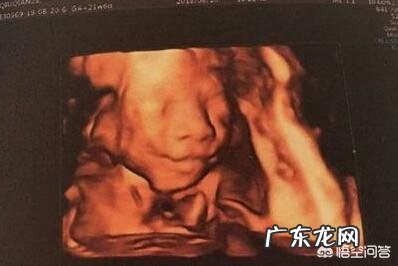

随着科普的普及,宝妈们一般会在孕20-24周左右做四维B超,进行胎儿畸形排除和拍几张胎儿图片做纪念 。但是很多宝妈发现四维照上的胎儿太丑了,尤其是颜面部特别大,题主重点讲到了嘴巴和鼻子 。

怀孕6个月,宝宝的四维拍照嘴巴和鼻子都好大,生出来后是不是很丑?为什么?很多妈妈6个多月的时候做四维检查,宝宝的照片总是鼻子嘴巴特别大,又大又扁,看起来丑丑的,特别担心宝宝出生后也会很丑;其实妈妈们是不需要担心的,宝宝的大嘴巴大鼻子都跟遗传有关,只要爸爸妈妈鼻子嘴巴不是很大,宝宝一般都不会特别大的 。